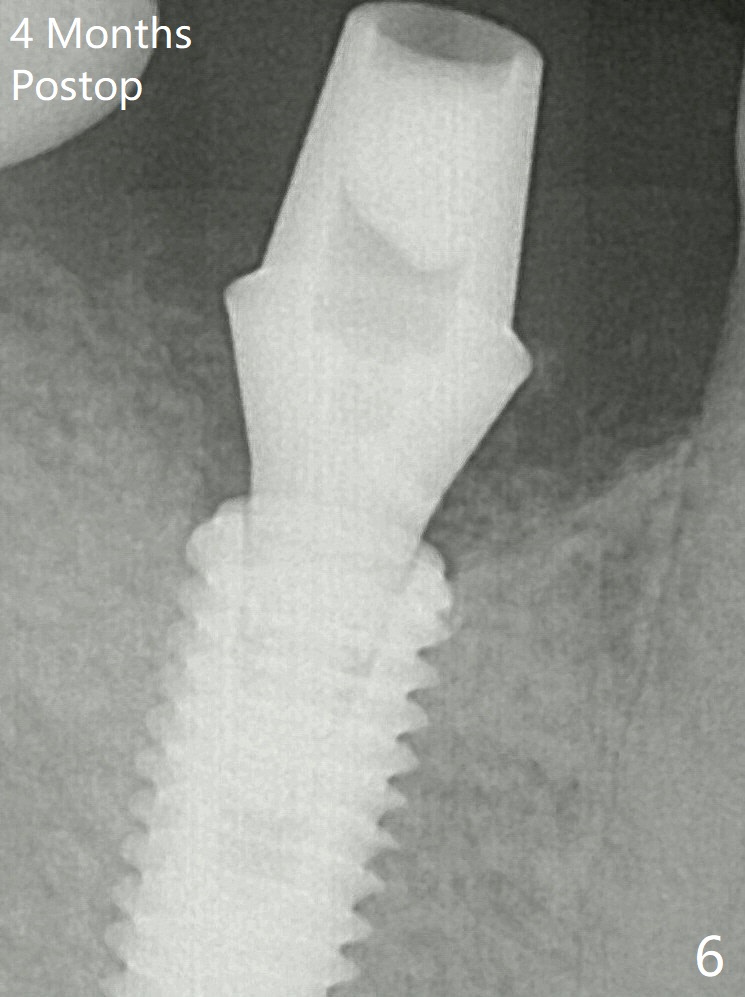

After insertion of a 5.7x5.5(3) mm abutment, Vanilla Graft is placed (Fig.5 * with 2 mm buccal gap). The abutment with a provisional is loose 4 months postop (Fig.6). The abutment screw is loose and fractured 8 and 11 months post cementation, respectively (Fig.7). The fractured screw seems to be loose within the implant well and is easily re-winded out. When the crown/abutment is loose 2nd time 1 year 7 months post cementation (Fig.8 taken post retightening), the screw at #19 fractures. The tooth #2 needs a crown. The patient cannot use the anterior teeth, since the teeth #8 and 9 have root fracture. Can extraction and bone graft increase bone height? The screw re-fractures 9 months later (Fig.9).